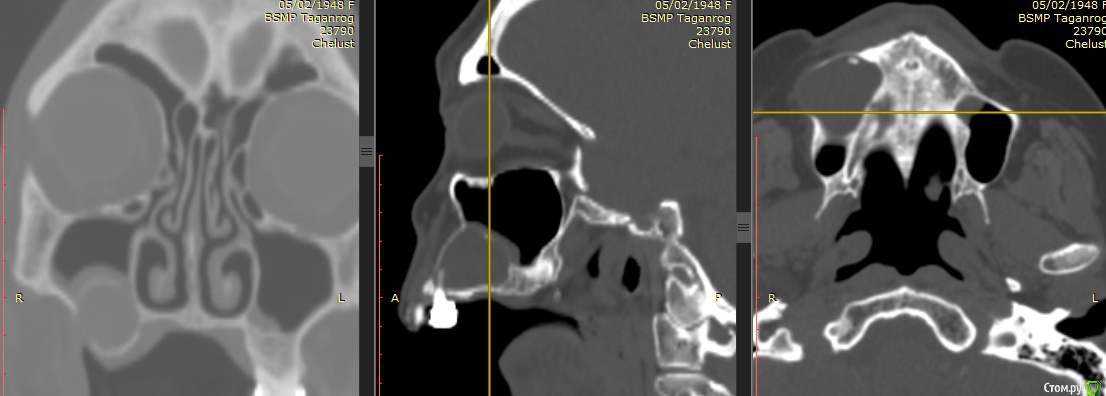

carloss Опубликовано 1 октября, 2015 Поделиться Опубликовано 1 октября, 2015 http://savepic.ru/7886604.jpg http://savepic.ru/7866124.jpg http://savepic.ru/7924495.jpg http://savepic.ru/7928591.jpg в лунке сначала биоосс, поверх биосс-коллаген 15 Ссылка на комментарий

carloss Опубликовано 1 октября, 2015 Автор Поделиться Опубликовано 1 октября, 2015 тут ситуация такая, что без графта в полость кисты, через пару месяцев высота уйдёт в ноль и придется идти на синус 1 Ссылка на комментарий

carloss Опубликовано 1 октября, 2015 Автор Поделиться Опубликовано 1 октября, 2015 кисты дают экспансивный рост в пределах губчатого вещества, кортикалка не затрагивается и уж точно не мигрирует в полость пазухи))) Вся заслуга исключительно карлоса))не очень понял что вы имели ввиду, но тут киста с кортикалкой проросла таки в пазуху.. это точно не лунка, размеры тут побольше.. а графтом этот объем сохранится и после 1 Ссылка на комментарий

carloss Опубликовано 1 октября, 2015 Автор Поделиться Опубликовано 1 октября, 2015 имел в виду то, что переапекальные абсцессы увеличиваются разрушая губчатое вещество, кортикальный слой как правило истончается и появляется сиптом так называемый пластмассовой игрушки, но вздутия при этих кистах не должно быть в отличие от опухолей. Поэтому киста просто бы проросла внутрь пазухи, но не сместила бы её дно.значит я правильно вас понял.. но вы ошибаетесь.. эта ветка пример того, как кортикалка сместилась в пазуху.. ещё пример http://forum.stom.ru/topic/29183-sinus-lifting-v-polost-kisty/ ну и вообще я такое часто вижу.. раньше правда не забивал графтом.. и всё уходило в ноль 2 Ссылка на комментарий